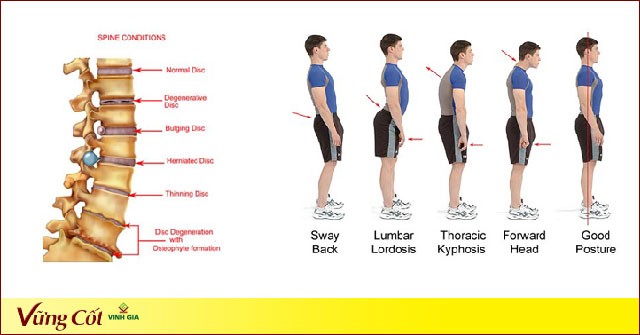

Thoái hóa đốt sống cổ là do thoái hóa hệ thống xương cột sống vùng cổ, gây bởi các nguyên nhân khác nhau như chế độ dinh dưỡng, công việc, lao động, hoạt động, tuổi tác. Nó là quá trình gây bệnh ở các đốt sống và xương đốt sống cổ, đầu tiên là sự suy giảm mật độ ở các đốt xương, cộng thêm sự hư khớp ở các thân đốt, đĩa liên đốt tới các màng, dây chằng, hậu quả là tình trạng thoái hóa các đốt sống cổ, thoát vị đĩa đệm cột sống cổ gây đau vùng cổ xuất hiện, nhất là khi hoạt động hoặc tác động vùng cổ. Nói cách khác, đây là bệnh của quá trình lão hóa tự nhiên cùng với sự chăm sóc xương khớp chưa đầy đủ kết hợp với 1 trong các yếu tố thuận lợi tác động. Bởi vậy, bệnh này rất thường gặp ở độ tuổi trung niên, trong khoảng từ 30-50 tuổi.

- Các yếu tố được cho là thuận lợi gây thoái hoá cột sống cổ là dị dạng bẩm sinh đốt sống, chấn thương và vi chấn thương hoặc là bệnh nghề nghiệp như làm nhân viên văn phòng, IT, thợ may, diễn viên xiếc, những người phải mang vác nặng, v.v…